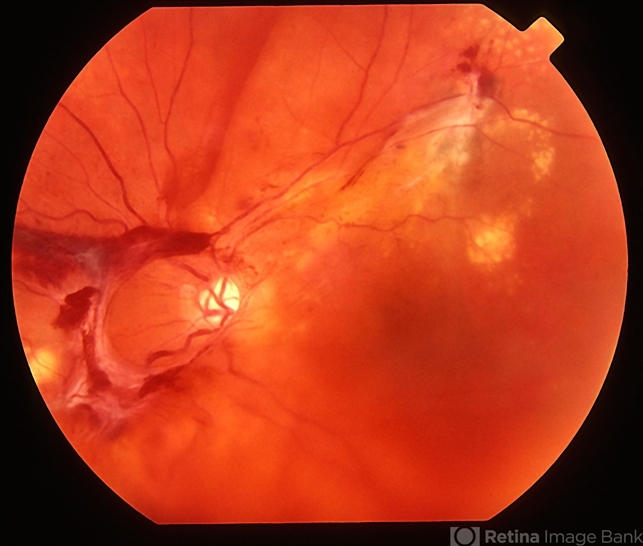

By Alex P. Hunyor, MD By Alex P. Hunyor, MD

Co-author(s): From the slide collection of Dr ABL Hunyor

- Uploaded on Jan 11, 2013.

- Retinal vein occlusion

- Condition/keywords

- central retinal vein occlusion (CRVO), laser treatment

- Imaging device

- Fundus camera

- Extensive NVD, NVE and vitreous haemorrhage complicating previous attempted laser-induced chorioretinal anastomosis for CRVO, left eye - color image.